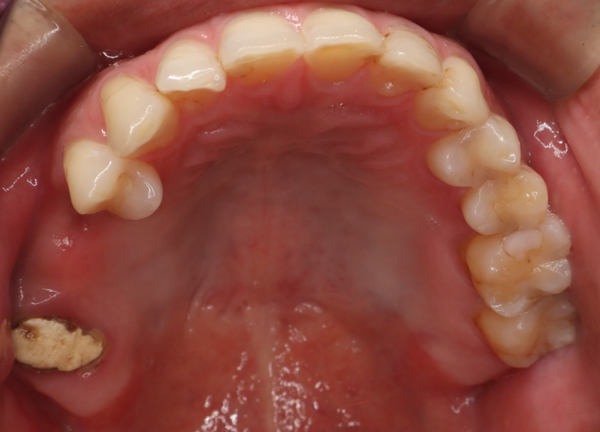

治療の経緯

右上の歯が取れたので、噛めるようにしたい

治療方法

奥歯は歯根破折していたため、抜歯をし、骨が少なかったため上顎洞にサイナスリフトを行い、骨を補填してインプラントを埋入しました。インプラントブリッジにて被せ物を作りました。

治療期間 動的期間6ヶ月

費用 インプラント埋入2本 600,000円

サイナスリフト  330,000円

セラミックのブリッジ(クラウン3本分)  450,000円

合計   1,380,000円

治療によるリスク インプラントは歯周病に弱いため、歯周病にかかると悪化する可能性があります